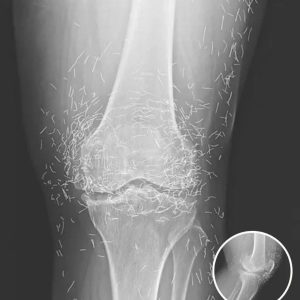

GOLD NEEDLE MYSTERY Doctors Shaken By Secret Objects Hidden Inside Womans Knee XRay For Decades

When a 65-year-old woman in South Korea sought medical help for chronic knee pain, doctors expected to see typical signs of Osteoarthritis. Instead, her X-rays revealed something…